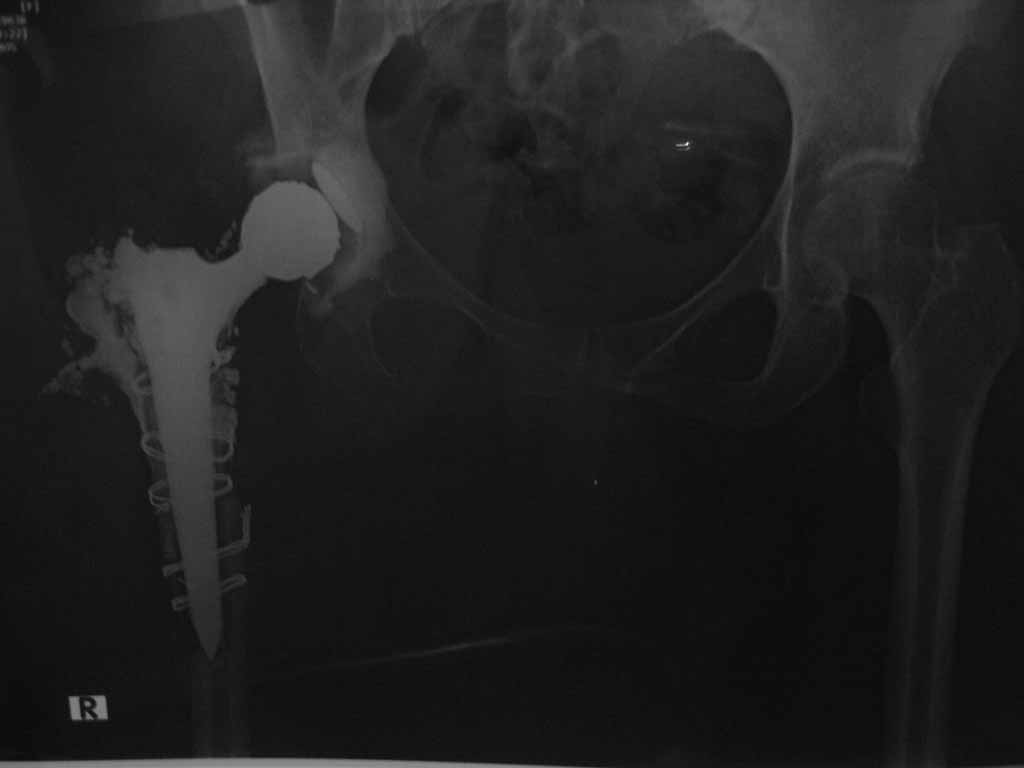

В августе 2010 года оперирована по поводу коксартроза пр ТБС Тотольное эндопротезирование. Видемо, во время обработки бедренного канала треснула вся проксимальная часть бедра. В послеоперационном периоде опер.рана не заживала..открылся свиш. нагноение!!!

К нам поступила 30.05.2011 г . В настоящая время серозо-гнойное отделяемое из раны.

Оперирована.2.06.2011г. Удален эндопротез, серкляжи и несколько секвесторы (проксимальный конец бедра). Образовался большой дефект. Дефект заполнен цементным спейсером. Активный дренаж.